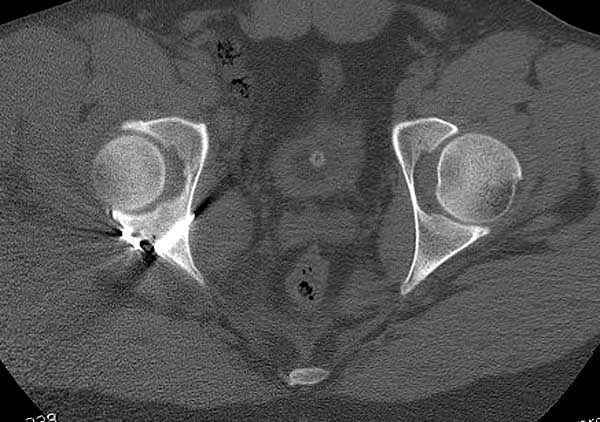

11:50 больной в послеоперационной, рентгенограмма N7, компьютерная томограмма в тот же день N8-10

Кроме вывиха виден перелом задней стенки, насчет задней колонны не уверен (видна линия перелома дистальнее ацет. крыши - подвздошная проекция или СТ помогли бы прояснить ситуацию). Поэтому с такой ситуации только закрытое вправление без рефиксации фрагмента задней стенки может привести к рецидиву вывиха (с чем имел неприятность столкнуться не так давно).

На первый взгляд, бедро надо вправить, наложить вытяжение, и дообследовать - Judet views, CT вертлужной впадины, чтобы оценить дефект задней стенки. Вероятно, придется делать остеосинтез заднего края.